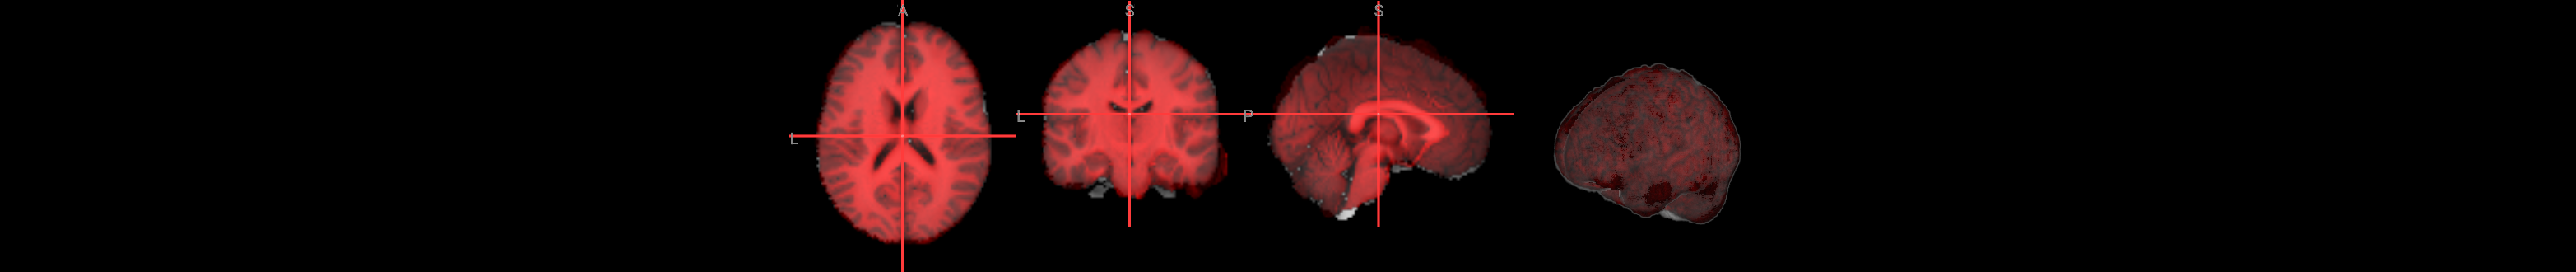

# functional run 1

nv = NiiVue()

nv.load_volumes([{"path": func1_image}])

nv

Image(url='https://raw.githubusercontent.com/NeuroDesk/example-notebooks/refs/heads/main/books/images/afni_preproc_func1.png')